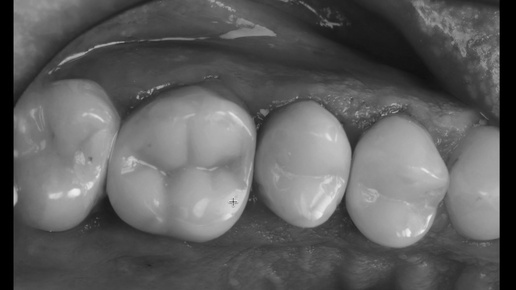

Пациент не дождался приёма и начал лечение зуба в другой клинике - разочаровался